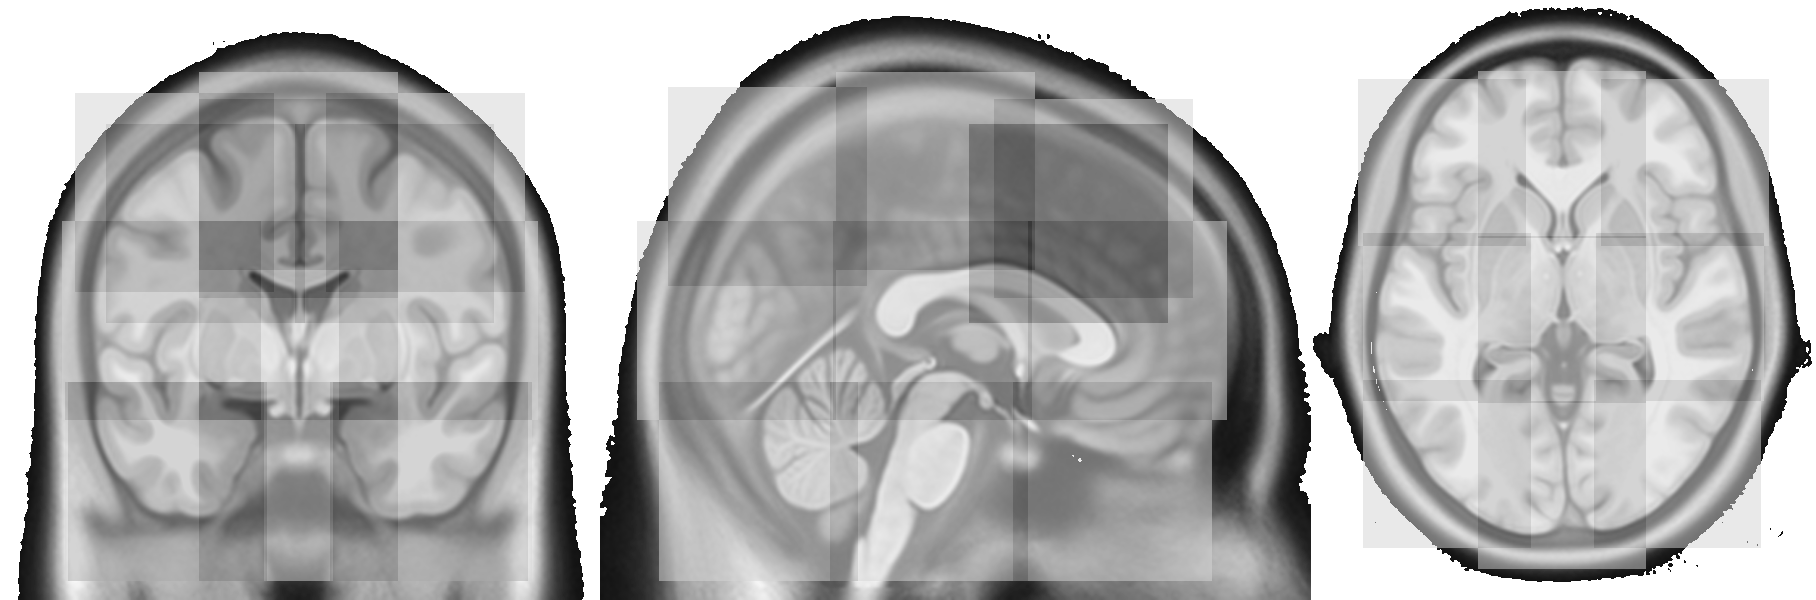

Refer to caption

Figure 4: Coronal (left), sagittal (middle), and axial slice (right) of the 128x128x128 voxel patches resulting from the optimized patch positioning. For reference, the T1 template of CAT12, upsampled to the utilized resolution of 0.5mm, is shown in the background.

Before applying patches from the right hemisphere to the UNet, we apply flipping along the sagittal axis such that they resemble left hemisphere patches. The resulting prediction is then flipped back. This approach reduces the number of effective patch positions individual UNets need to be trained for from 27 to 18.

Close to the border of a patch, the accuracy of the prediction typically decreases. Therefore, predictions close to the border of a patch are weighted less via Gaussian importance weighting [23] during accumulation of the final prediction containing 336x384x336 voxels.